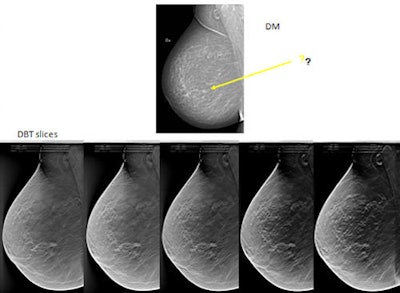

While individual screening is most likely be the optimal weapon to wield in the fight against breast cancer, the evidence to support large-scale implementation remains scarce, and limited health budgets also hamper such programs. The compromise of "a middle way," using evidence-based 2D mammography screening that has proved a cost-effective method for most women, would seem a practicable tool. But 3D mammography (digital breast tomosynthesis [DBT]), which is considered to have clear advantages for detecting cancer in dense breasts, is now emerging as a potentially viable population screening method.

During their design, it was believed that the trials would show that 3D mammography would prove most beneficial for screening women with dense breast tissue, explained Zackrisson, who is presenting at today's "ECR meets Nordic countries" session. However the first results are now in from all three trials, and, startlingly, additional cancers have been found with 3D mammography in all types of breast, with no clear trend for dense breasts categorized as BI-RADS 3 and BI-RADS 4, she said.

DBT may provide an alternative to 2D mammography, given that it seems to already be detecting additional cancers in all breast types. However, the question of changing screening methods for the general population is a complex issue that needs long-term trials to ascertain certainty of improved results. Such long-term trials will establish cost-effectiveness in terms of false-positive rates, human resources required, reading time, and overdiagnosis of indolent slow-growing cancers that wouldn't have caused harm or death during the individual's life time.